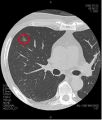

Automatic extraction of laesio part on lung CT images

We develop a Computer Aided Diagnosis(CAD) system which extracts laesio parts automatically.